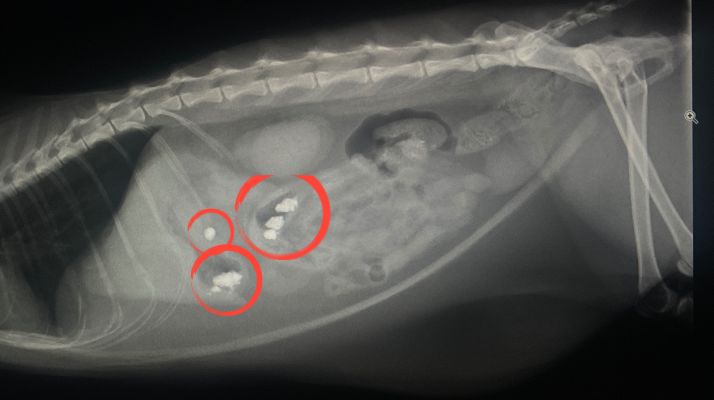

また外袋を一緒に飲み込むと、腸に詰まってしまうる腸閉塞を起こしてしまうこともあります。

カイロを袋ごと飲み込むと、胃や腸に詰まることがあります。

詰まると強い嘔吐や食欲不振が続き、重い場合は手術が必要になることもあります。